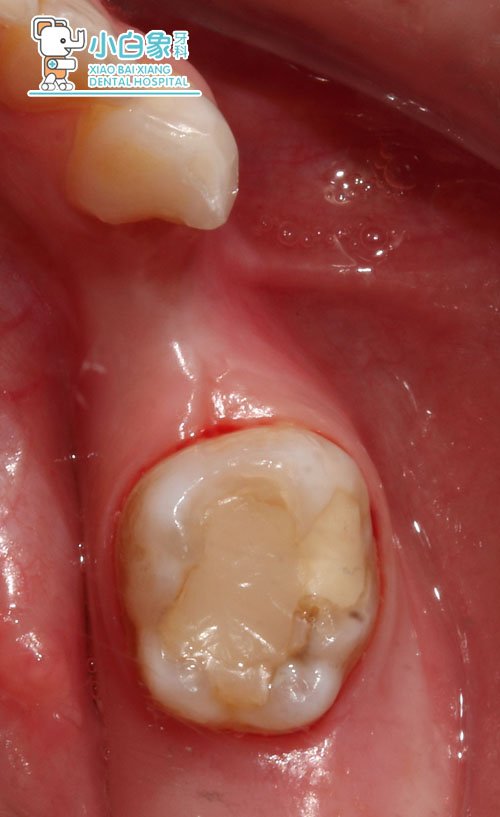

检查:74缺失,牙龈无红肿,龈合距尚可。75合面见大面积牙体色材料,叩(-),牙龈无红肿。

治疗过程:75试戴预成冠,取模,制作间隙保持器。